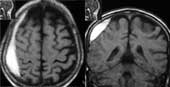

Рис. 1. Эпидуральная гематома в проекции передне-верхних отделов передней черепной ямки слева. Подострая стадия. Т2 режим.